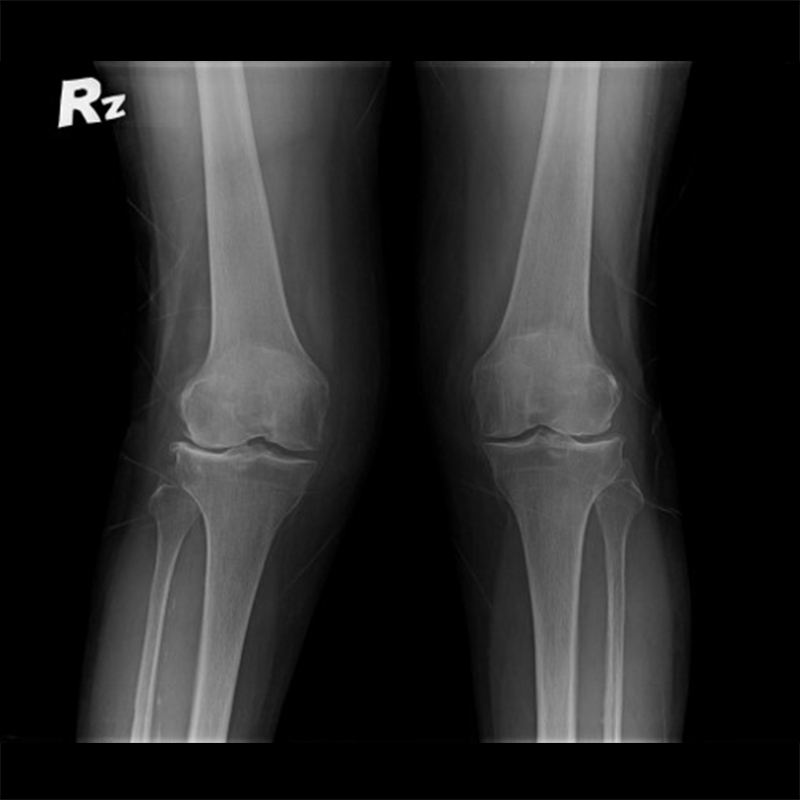

機器手臂手術 首頁 案例分享 膝關節手術 機器手臂手術 蔡女士 78歲 術前 術後 陳女士 70歲 術前 術後 術前 術後 ANGEVINE女士 73歲 術前 術後 U.S.A Mark 73歲 術前 術後 藍女士 78歲 術前 術後